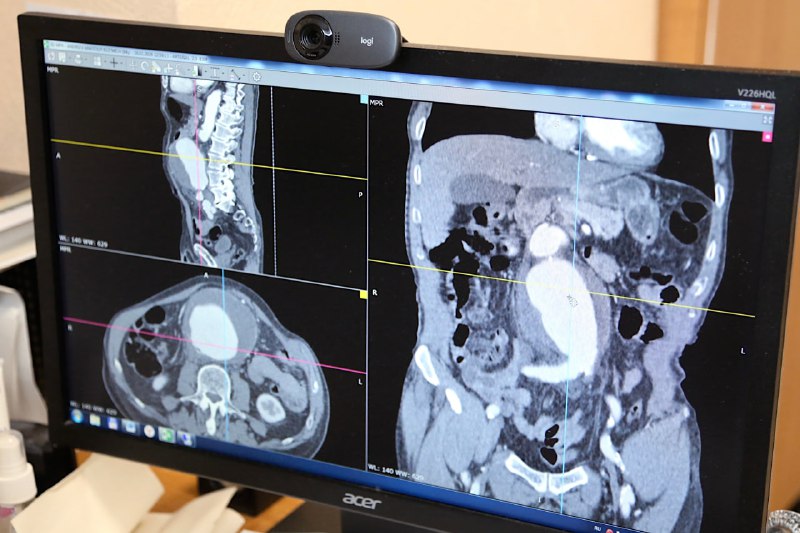

Врачи трех клиник спасли неудачно почистившего снег новгородца